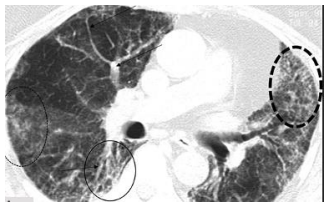

An 85-year-old man, also without comorbidities, presented with fever, dry cough, and exertional dyspnea. While his initial chest radiograph showed minor peripheral lung opacities, HRCT imaging later revealed signs of fibrosis, including ground-glass opacities and fine honeycombing. He was treated with corticosteroids, multivitamins, and oxygen therapy. Although his symptoms improved, he continued to experience exertional breathlessness at discharge and was advised to undergo pulmonary rehabilitation.

Fig 2: An axial HRCT image of an 85-year-old man with post-COVID-19 pulmonary fibrosis shows extensive reticulations, prominent pulmonary vessels, volume loss, patchy consolidation, and a fine honeycomb appearance, particularly in the periphery.